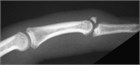

A patient arrives with a tender fingertip injury with a noticeable deformity. There is a history of a sudden resisted flexion of the distal interphalangeal (DIP) joint, such as when the fingertip is struck by a ball or jammed against a stationary object, resulting in pain and tenderness over the dorsum of the base of the distal phalanx. This injury can occur with relatively minor trauma (such as jamming a finger while reaching for a light switch in the dark) or even as a result of a direct blow to the dorsum of the finger. It may or may not be accompanied by swelling and ecchymosis over the DIP joint. When the finger is at rest or held in extension, the injured DIP joint remains in slight or moderate flexion (Fig. 106.1).